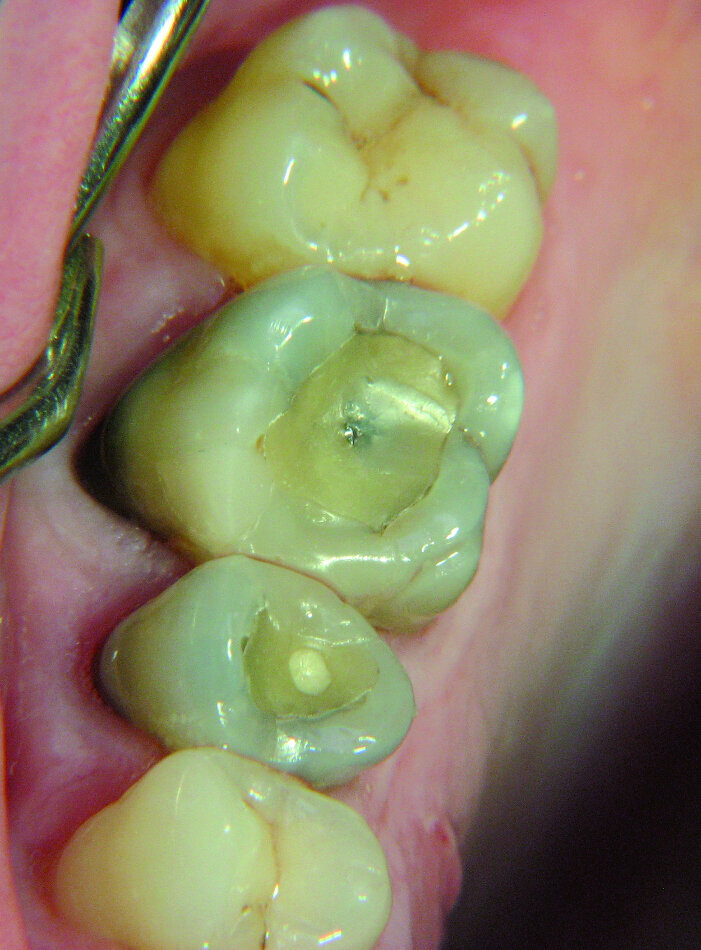

Les deuxièmes molaires gauches peuvent montrer l’harmonie des relations avec les membres de notre famille. Une de mes jeunes patientes se démenait pour faire face à une relation triangulaire permanente au sein de sa famille. Un traitement endodontique était indiqué pour sa deuxième molaire supérieure gauche, alors que l’ensemble des dents ne présentait pratiquement aucune lésion carieuse (Fig. 12). Le frère, qui n’avait pas été confronté à la situation de sa soeur, ne présentait aucun problème dentaire. Dans ce contexte, je voudrais souligner que les dents reflètent les circonstances de la vie selon la perception subjective de la personne concernée. Pour nous dentistes, les troisièmes molaires sont généralement d’un intérêt secondaire, contrairement aux chirurgiens et aux endodontistes qui peuvent s’enorgueillir des canaux radiculaires de formes bizarres parfaitement obturés dans ces dents. D’un point de vue holistique toutefois, les troisièmes molaires expriment l’énergie interne d’un individu (Fig. 13). La troisième molaire supérieure droite correspond à nos efforts d’intégration dans le monde physique et le monde spirituel. La troisième molaire supérieure gauche représente la crainte du rejet de ces deux mondes. La troisième molaire inférieure droite est un baromètre de notre énergie physique.